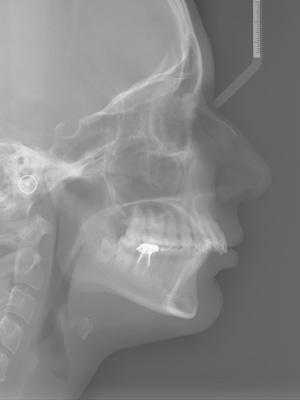

Дистальное положение челюстей на телерентгенограмме

- Компьютерная томография или 3D-проекция черепа. По ней можно оценить важные показатели для ортодонтического лечения: клиническую форму прикуса, размер и положение челюстей. Положение и соотношение зубов в костной ткани и ее объемы. Состояние и положение головки височно-нижнечелюстного сустава. Трехмерная модель черепа дает более точное представление о положении зубов и челюстей, чем классических 2D-снимок черепа в боковой проекции.

Для дифференциальной диагностики разновидности дистального прикуса проводится телерентгенография с последующим анализом и расчетом рентгенцефалометрических показателей; определение конструктивного прикуса; изготовление и исследование диагностических моделей челюстей. С целью оценки состояния элементов височно-нижнечелюстного сустава и жевательных мышц используется рентгенография или томография ВНЧС, электромиография, реография.